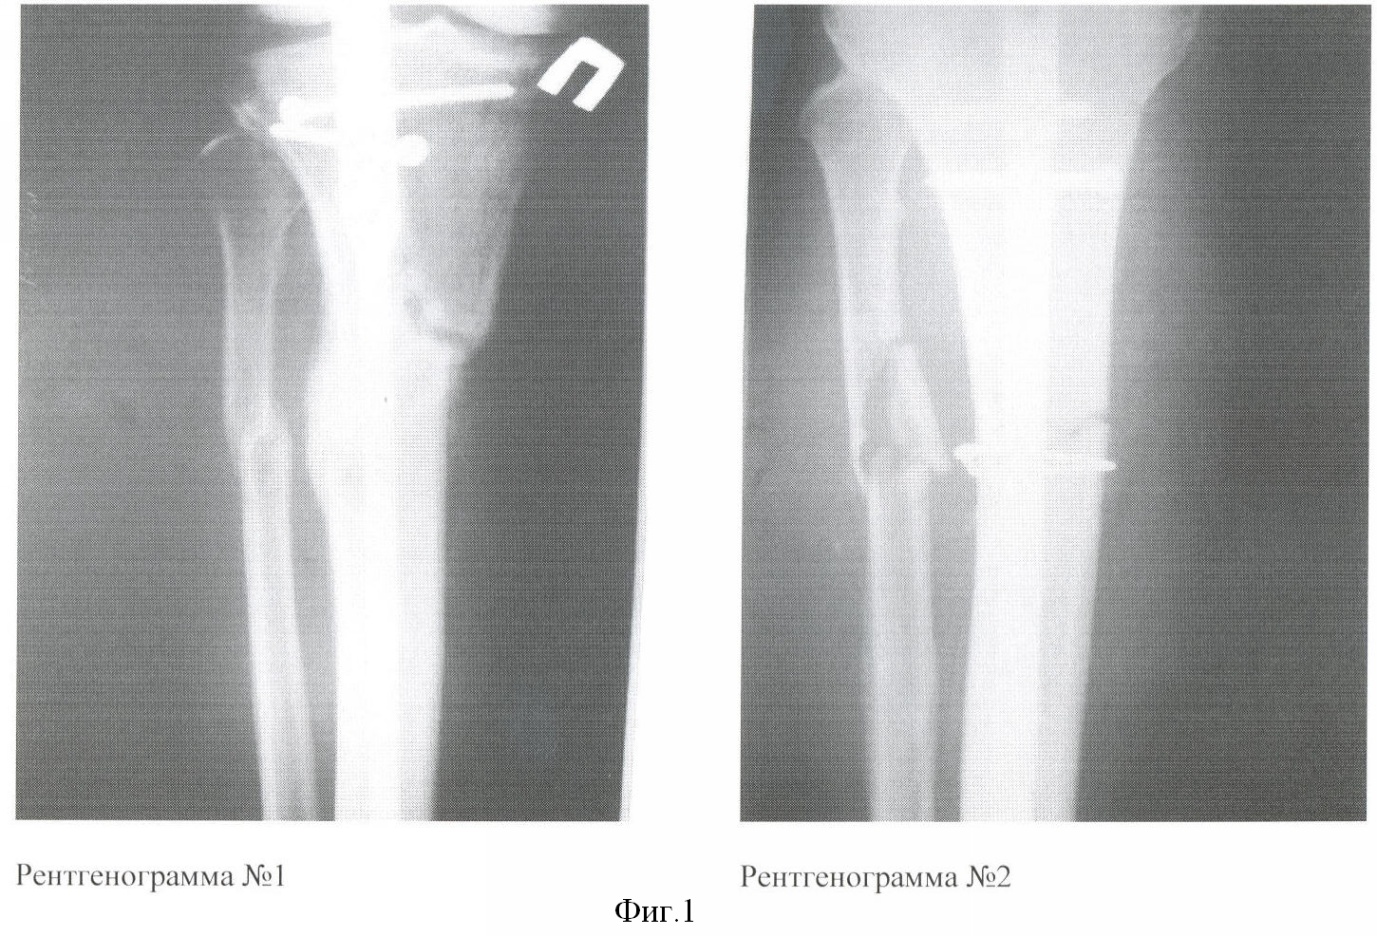

2) Больная Б. 38 лет поступила в клинику в первые сутки после травмы с диагнозом: Автотравма. Закрытый оскольчатый перелом костей обеих голеней в ср/3 со смещением. При поступлении больной было выполнено скелетное вытяжение обеих голеней. Клинический анализ крови при поступлении: гемоглобин – 116 г/л, эритроциты – 2.8*1012/л, лейкоциты – 7.3*109/л, палочкоядерные нейтрофилы – 3%, СОЭ – 10 мм/ч. Учитывая множественный и многооскольчатый характер переломов, сохранение смещения отломков на скелетном вытяжении после рентгеноконтроля, через 3 суток после поступления было выполнено оперативное вмешательство – накостный остеосинтез большеберцовых костей обеих голеней. В ходе операции зоны переломов вскрывались в связи с невозможностью закрытой репозиции. На 2 сутки после поступления у больной был выполнен забор 40 мл костного мозга из гребня подвздошной кости для культивирования АМСК. Послеоперационный период протекал без осложнений, послеоперационные раны зажили первичным натяжением. Клинический анализ крови на 11-е сутки после операции: гемоглобин – 110 г/л, эритроциты – 2.7*1012/л, лейкоциты – 7.6*109/л, палочкоядерные нейтрофилы – 5%, СОЭ – 13 мм/ч. Через 12 дней после операции больной были введены 50 млн АМСК в зону перелома левой большеберцовой кости (в зону наибольшего относительного дефекта кости по сравнению с правой конечностью) под рентгеноконтролем. После введения АМСК местных и общих патологических реакций организма не наблюдалось. Результаты лечения представлены на фиг.2.

Фиг. 2

– Рентгенограмма 3 – лечение с применением АМСК. Оскольчатый перелом обеих костей ср/3 левой голени со смещением. 8 недель после операции (накостный МОС б/берцовой кости с дополнительной фиксацией проволочным серкляжем). На снимке видна выраженная периостальная мозоль в зоне имплантации АМСК.

– Рентгенограмма 4 – лечение без применения АМСК. Оскольчатый перелом обеих костей ср/3 правой голени со смещением. 8 недель после операции (накостный МОС б/берцовой кости). На снимке отсутствуют признаки сращения б/берцовой и м/берцовой костей.

При выписке больной были даны стандартные рекомендации – постельный режим, передвижение на коляске, исключение осевой нагрузки на обе ноги. Через 8 недель после операций был выполнен рентгеноконтроль обеих голеней, на рентгенограммах отмечалось выраженная периостальная мозоль в зоне имплантации АМСК в левую голень. Лечение без применения АМСК: через 8 недель отсутствовали признаки сращения б/берцовой и м/берцовой костей правой голени – фиг. 2, рентг. 4). Полная консолидация костей левой голени была констатирована через 3 мес после операции, в то время как в правой голени сращение большеберцовой кости не наступило, а через 12 мес после операции там сформировался ложный сустав.